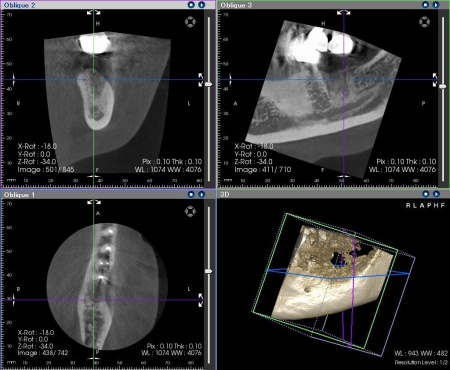

抜歯後の骨の状態を確認しています。

インプラントの埋入設計をしました。